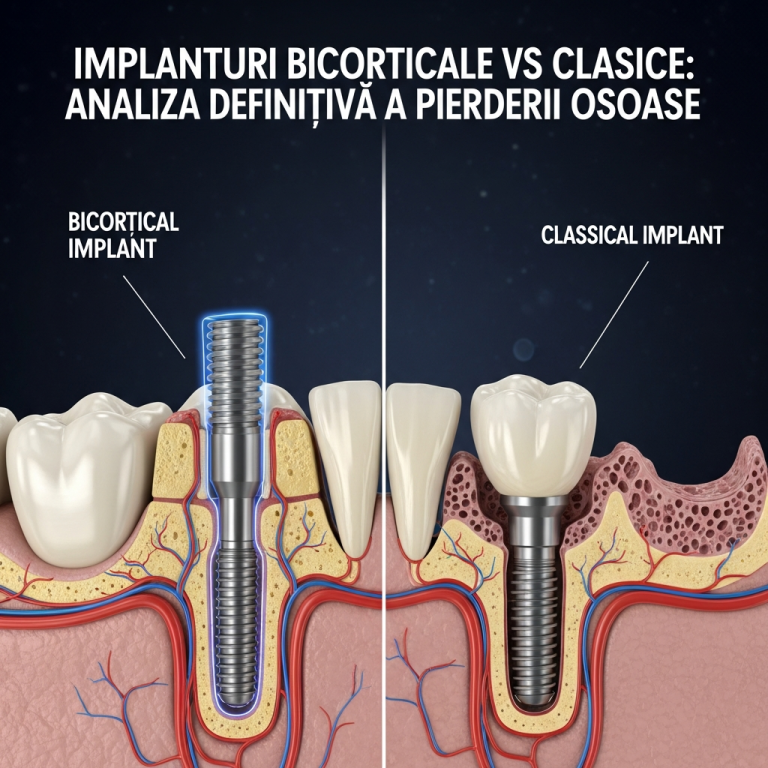

Implanturile dentare bicorticale, ancorate în osul bazal dens, reprezintă o soluție avansată. În 2026, utilizarea zirconiului pentru aceste implanturi aduce beneficii semnificative, confirmate de studii recente.

Zirconiul este hipoalergenic și prezintă o afinitate excepțională pentru țesutul osos. Acest lucru minimizează riscul de reacție adversă și sprijină osteointegrarea stabilă, esențială pentru succesul pe termen lung al implantului bicortical.

Rezistență Mecanică Superioară

- Rezistă la presiunile puternice din zona bazală.

- Risc extrem de scăzut de fractură sau fisurare.

- Durabilitate dovedită în situații cu volum osos redus.

Reducerea Riscului de Periimplantită

Suprafața netedă și netezibilă a zirconiului împiedică aderența bacteriană mai eficient decât titanul. Studiile indică o rată mai mică de complicații inflamatorii periimplantare.